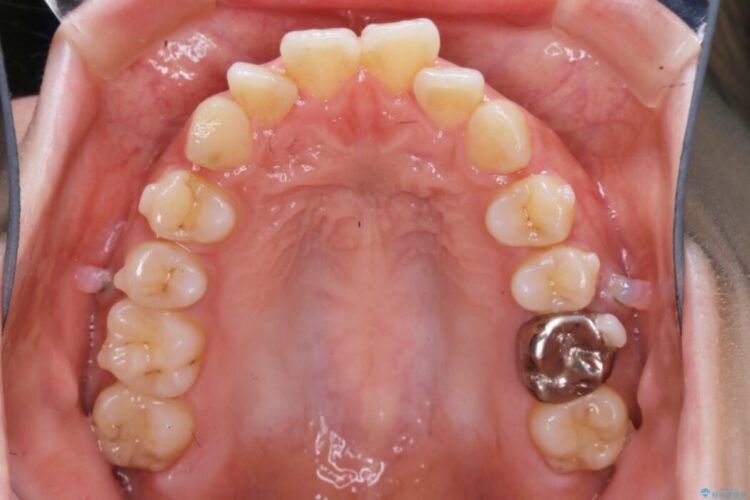

患者様のご希望によりインビザライン装置での治療を行いました。

インビザラインは歯を後ろへ動かす動き、非抜歯での矯正治療が得意なため、ワイヤー装置では難しいケースでも対応できる場合があります。

口元が後方に下がったことにより横から見たEラインが改善し、口元の印象が変わったと患者様にとても喜んでいただけました。